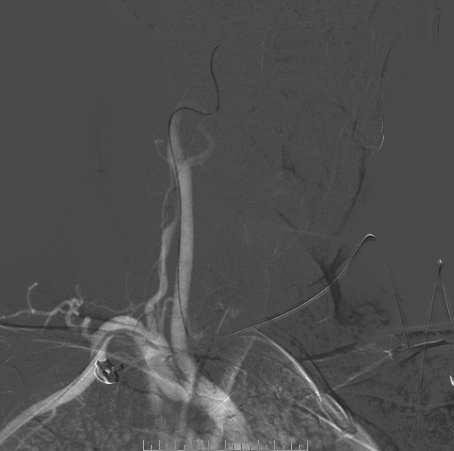

脑血管造影

左侧椎动脉造影

左侧颈总造影

右侧颈总造影:右侧大脑中动脉瘤